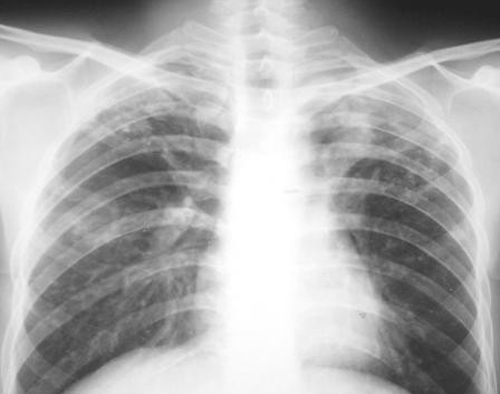

X胸片检查是诊断肺癌的最常用手段,往往用于检查中心型肺癌、周围型肺癌、孤立型细支气管肺泡癌、弥漫型细支气管肺泡癌等几种肺癌;CT检查可显示肺部0.2-0.3cm以上的小结节病灶,对肺癌的早期诊断有很大的价值。

X胸片检查不能查出所有的肺癌,如果是病灶位于支气管内或小于1cm,或病灶位于肺炎不、脊柱旁、心脏后等部位时,则往往不容易被胸部X线检查发现。